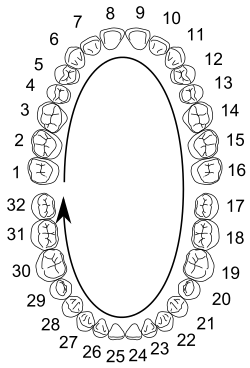

Among permanent teeth, 16 are found in the maxilla and 16 in the mandible, for a total of 32. The dental formula is 2.1.2.32.1.2.3. Permanent human teeth are numbered in a boustrophedonic sequence.

The maxillary teeth are the maxillary central incisors (teeth 8 and 9 in the diagram), maxillary lateral incisors (7 and 10), maxillary canines (6 and 11), maxillary first premolars (5 and 12), maxillary second premolars (4 and 13), maxillary first molars (3 and 14), maxillary second molars (2 and 15), and maxillary third molars (1 and 16). The mandibular teeth are the mandibular central incisors (24 and 25), mandibular lateral incisors (23 and 26), mandibular canines (22 and 27), mandibular first premolars (21 and 28), mandibular second premolars (20 and 29), mandibular first molars (19 and 30), mandibular second molars (18 and 31), and mandibular third molars (17 and 32). Third molars are commonly called "wisdom teeth" and usually emerge at ages 17 to 25.[6] These molars may never erupt into the mouth or form at all. When they do form, they often must be removed. If any additional teeth form—for example, fourth and fifth molars, which are rare—they are referred to as supernumerary teeth (hyperdontia). Development of fewer than the usual number of teeth is called hypodontia.